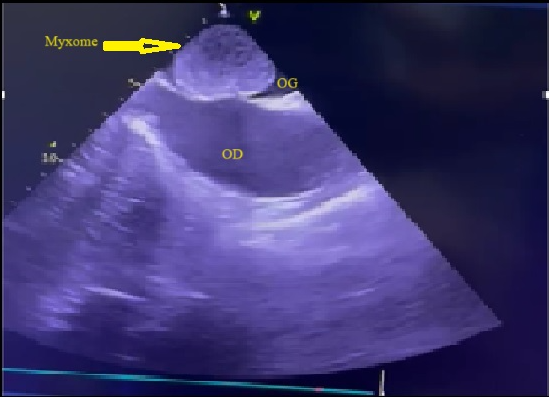

L’électrocardiogramme s’inscrivait en rythme sinusal régulier avec une fréquence cardiaque à 74bpm. L’échocardiographie transthoracique a mis en évidence une volumineuse masse intra-atriale gauche mesurant 57mm x 42mm appendue au septum inter atrial, avec dilatation de l’oreillette gauche et de l’anneau mitral associée à une insuffisance mitrale sévère grade 4/4. Le diagnostic retenu était un probable myxome de l’oreillette gauche compliqué d’insuffisance mitrale sévère. Les caractéristiques de cette masse ont été confirmées à l’échographie cardiaque transœsophagienne (figure 1). La fonction systolique du ventricule gauche était préservée avec une dysfonction diastolique grade 2. Les pressions de remplissage du ventricule gauche étaient normales. Le bilan biologique n’avait noté aucune anomalie.

Figure 1 : Echocardiographie transoesophagienne en bi dimensionnelle incidence bicave montrant un myxome de l’oreillette gauche appendu au septum inter atrial (Cas clinique n°1). OG= oreillette gauche ; OD= oreillette droite